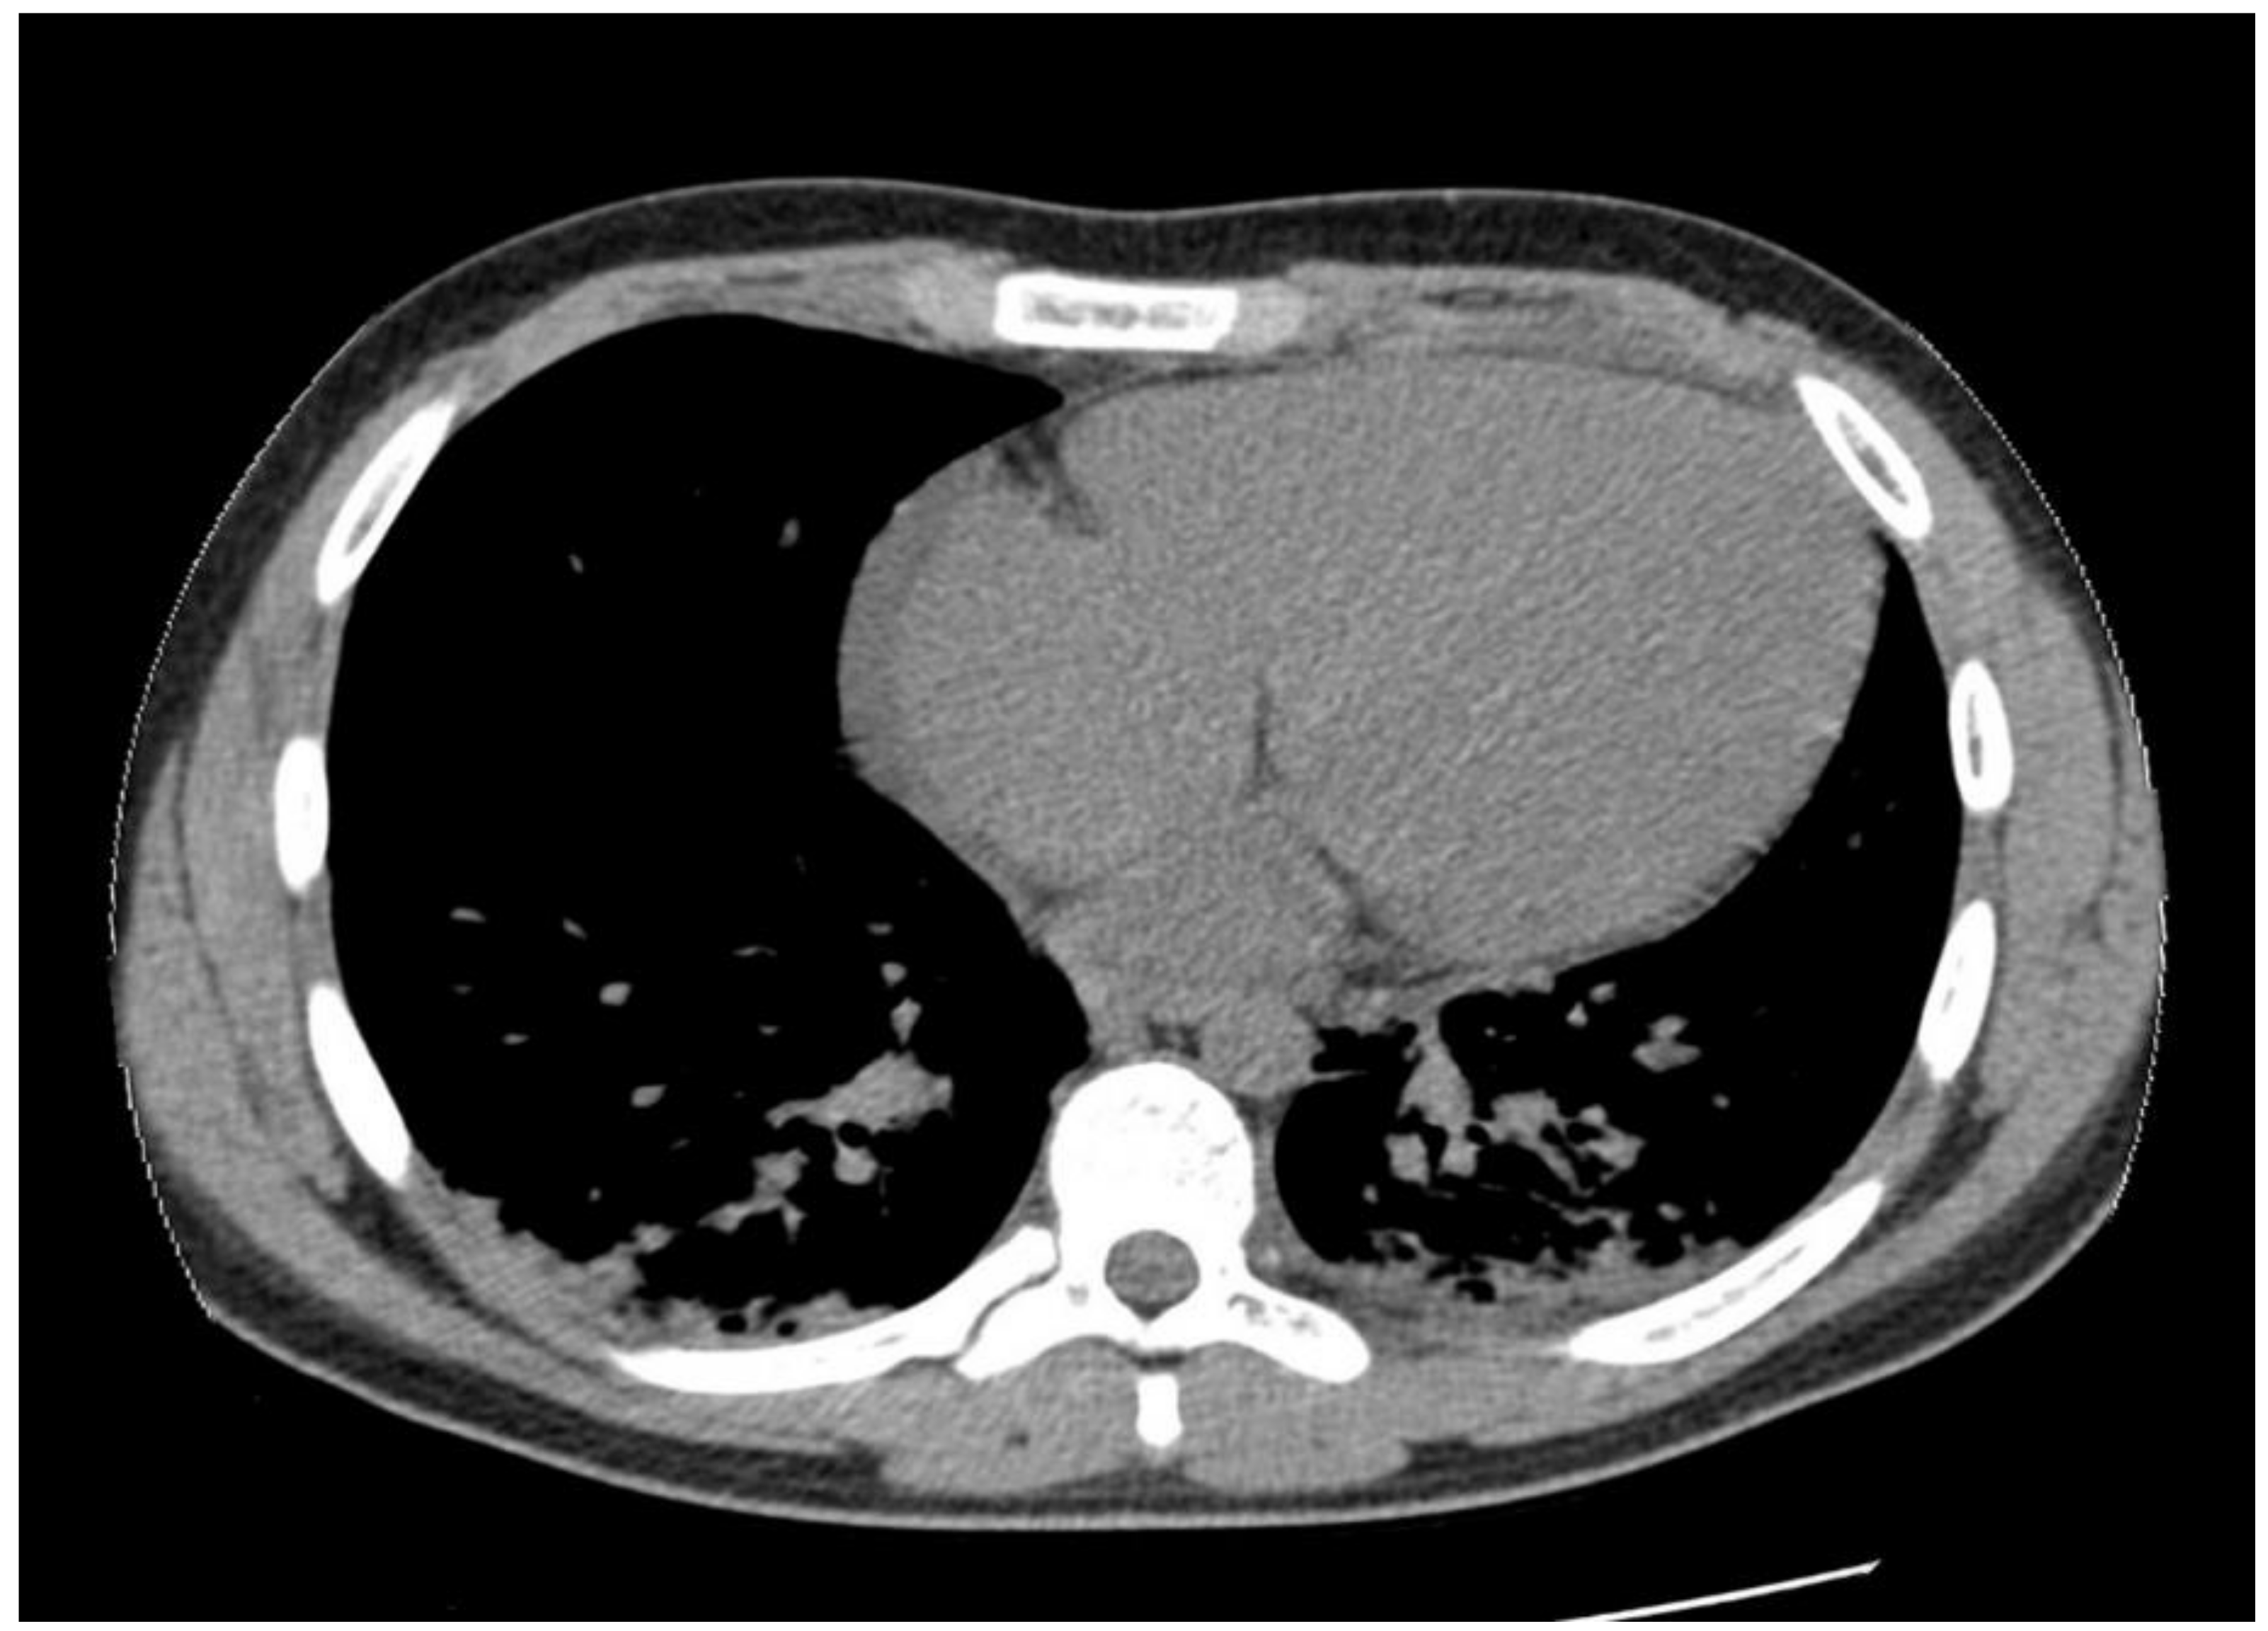

1.1. Case Presentation #1

1.2. Case Presentation #2